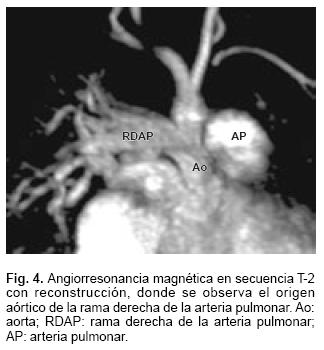

La radiografía de tórax mostró cardiomegalia grado III y flujo pulmonar aumentado. En el ecocardiograma (Fig. 1) se observó que la rama derecha de la arteria pulmonar (RDAP) nacía de la aorta ascendente. Había marcada hipertensión arterial pulmonar. Tenía mala función ventricular con fracción de eyección de 33%. El estudio hemodinámico (Figs. 2 y 3) demostró que la presión sistólica de la rama izquierda de arteria pulmonar era suprasistémica de 80 mm Hg y en la rama derecha era de 60 mm Hg, igual a la sistémica; se observó gran retardo del vaciamiento de la vena pulmonar izquierda; había un conducto arterioso permeable. La angiorresonancia magnética (Figs. 4 y 5) corroboró los diagnósticos y mediante la reconstrucción permitió ver una estenosis de la vena pulmonar superior izquierda. Por la edad de la paciente y la presencia de la obstrucción venosa pulmonar fija, se consideró candidata a cirugía.